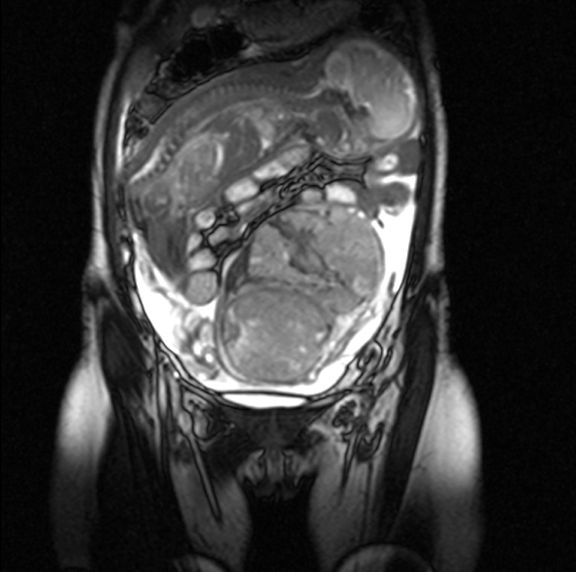

Lekarze odkryli również, że silne bóle brzucha są spowodowane tym, że podczas nieudanej próby przeprowadzenia aborcji doszło do pęknięcia macicy, a rozwijający się płód przedostał się w worku owodniowym do jelita. Niezwykłe zdjęcie z badania obrazowego obiegło media na całym świecie.

Płód rozwijał się w jelicie

Płód rozwijał się w jelicie © Facebook